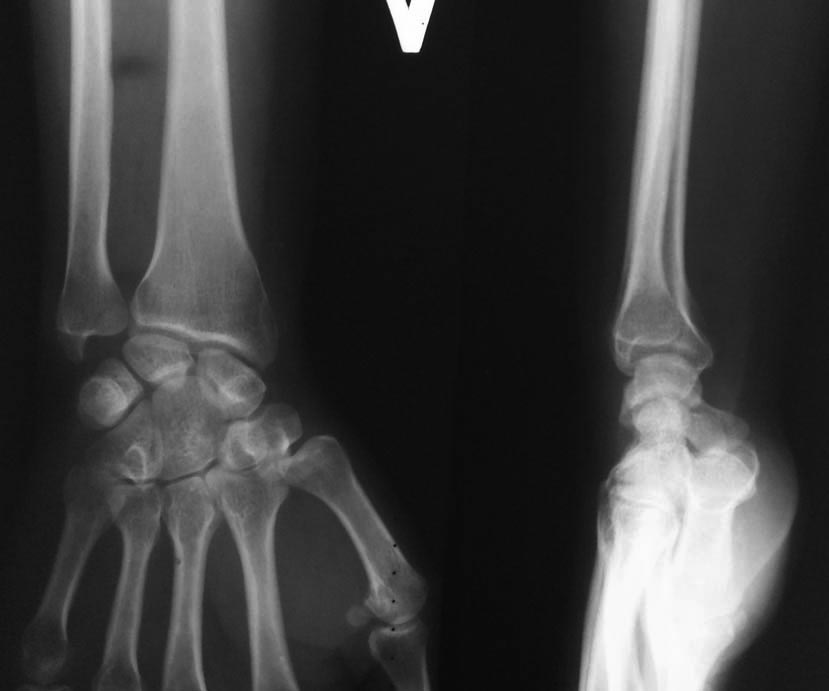

Rg-здоровой руки